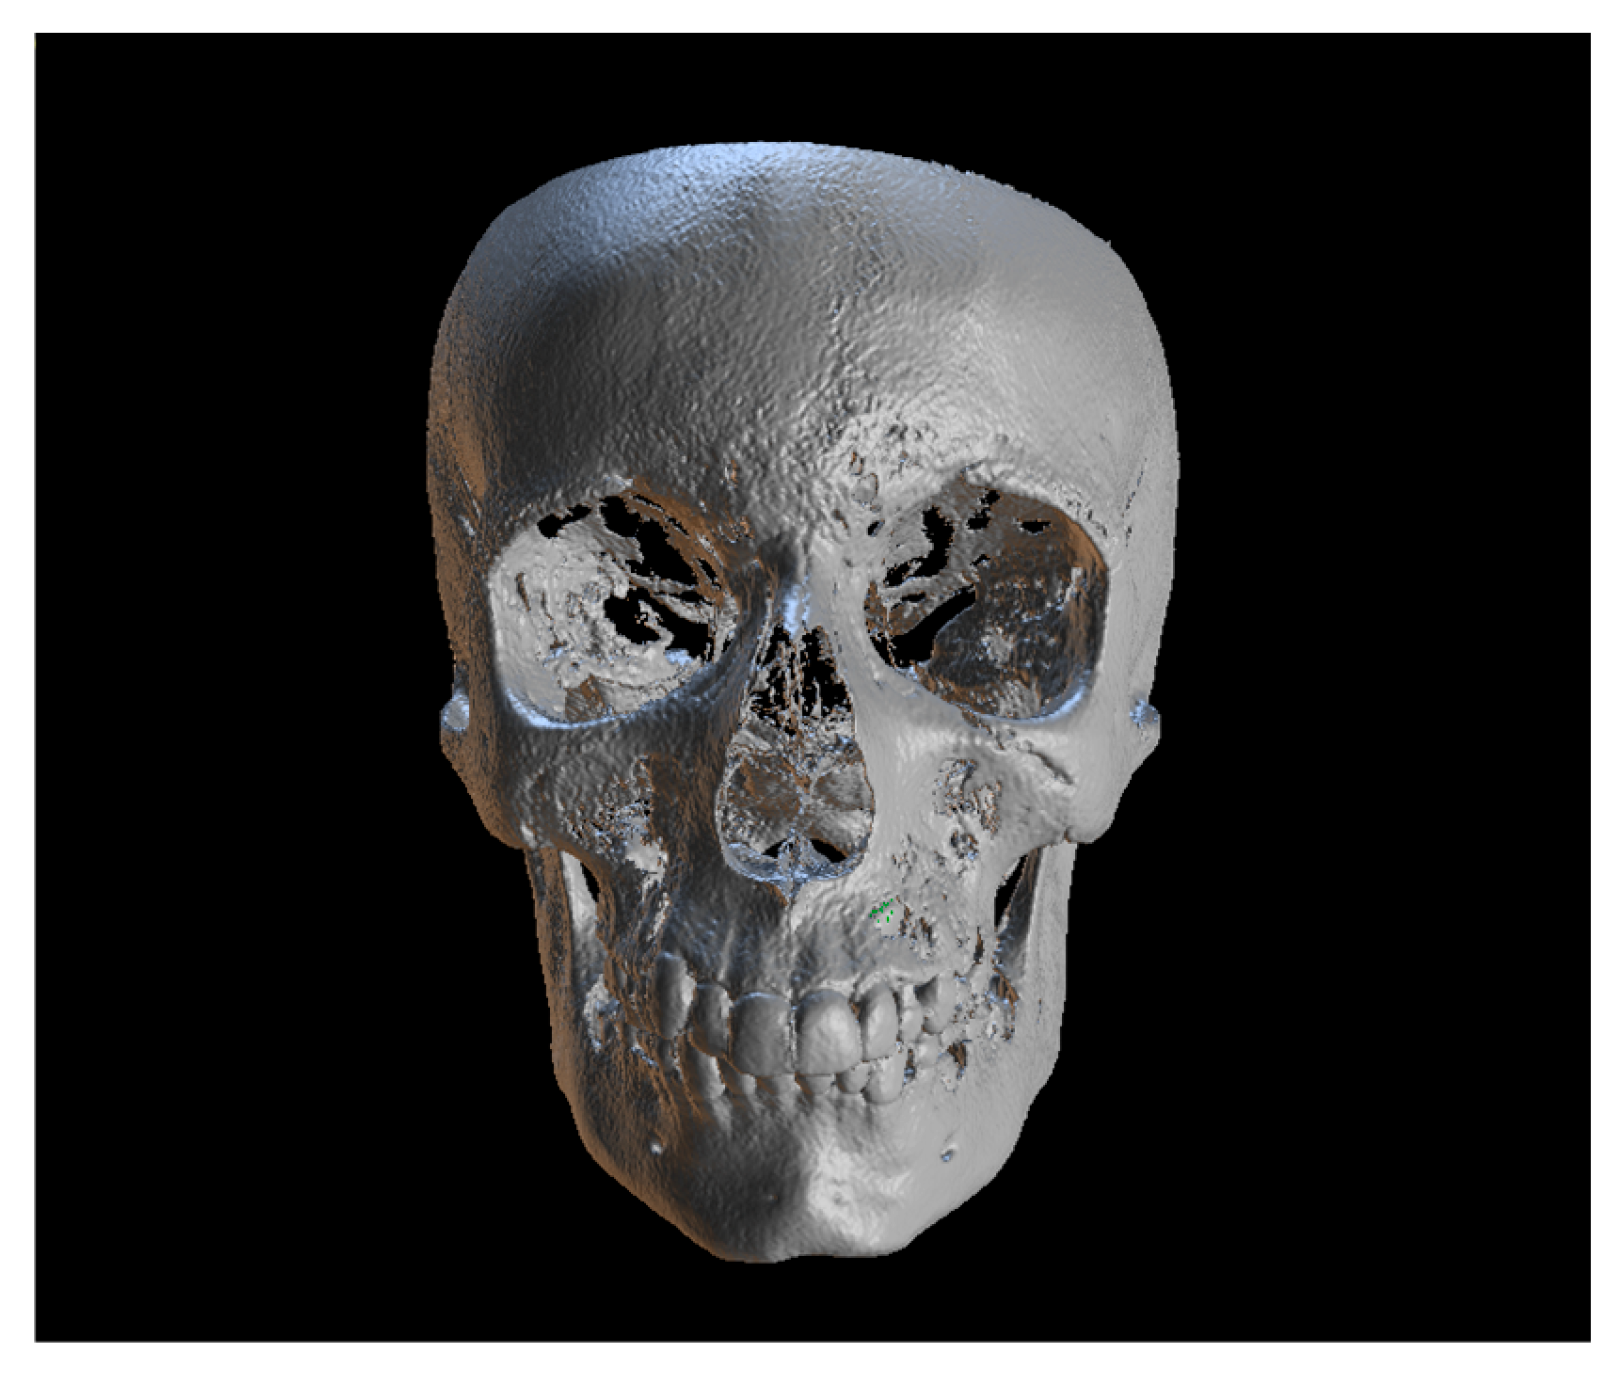

Since the IC is not visible in the initial STL, it was necessary to know its three-dimensional location. As performed in the other method, the initial CBCT scan (Figure 2) was opened in the program, and all teeth were segmented. Although Figure 2 shows the skull model, only the teeth segmentation is necessary for this method. A small cut was made to allow visualization of the IC (Figure 3).

Figure 2.

Initial CBCT scan.